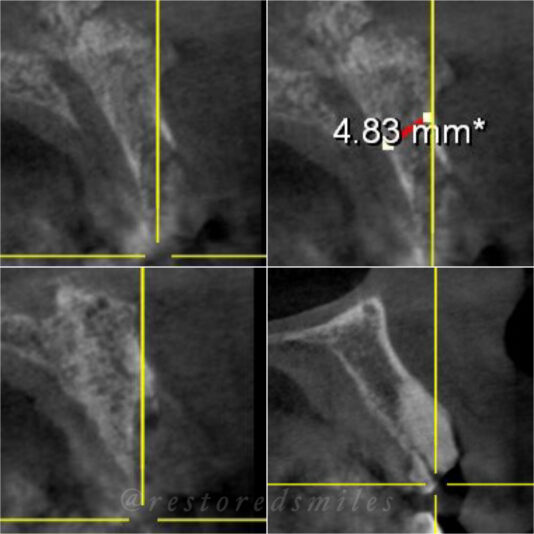

• This case I posted last year when I was planning. Here it is at 5 months, I am concerned about the buccal plate width at the mid/apical third. Clearly should have put this more lingual. Long term predictability?

1

• Looks good, right?!? Not once you see the cbct and create a larger full thickness flap. What would you do here? What are your options? This happened during one of our live surgery courses. Please leave a comment below on what you would do and a couple options we may have. After I recieve several comments I will post a follow up post next week…

Read more